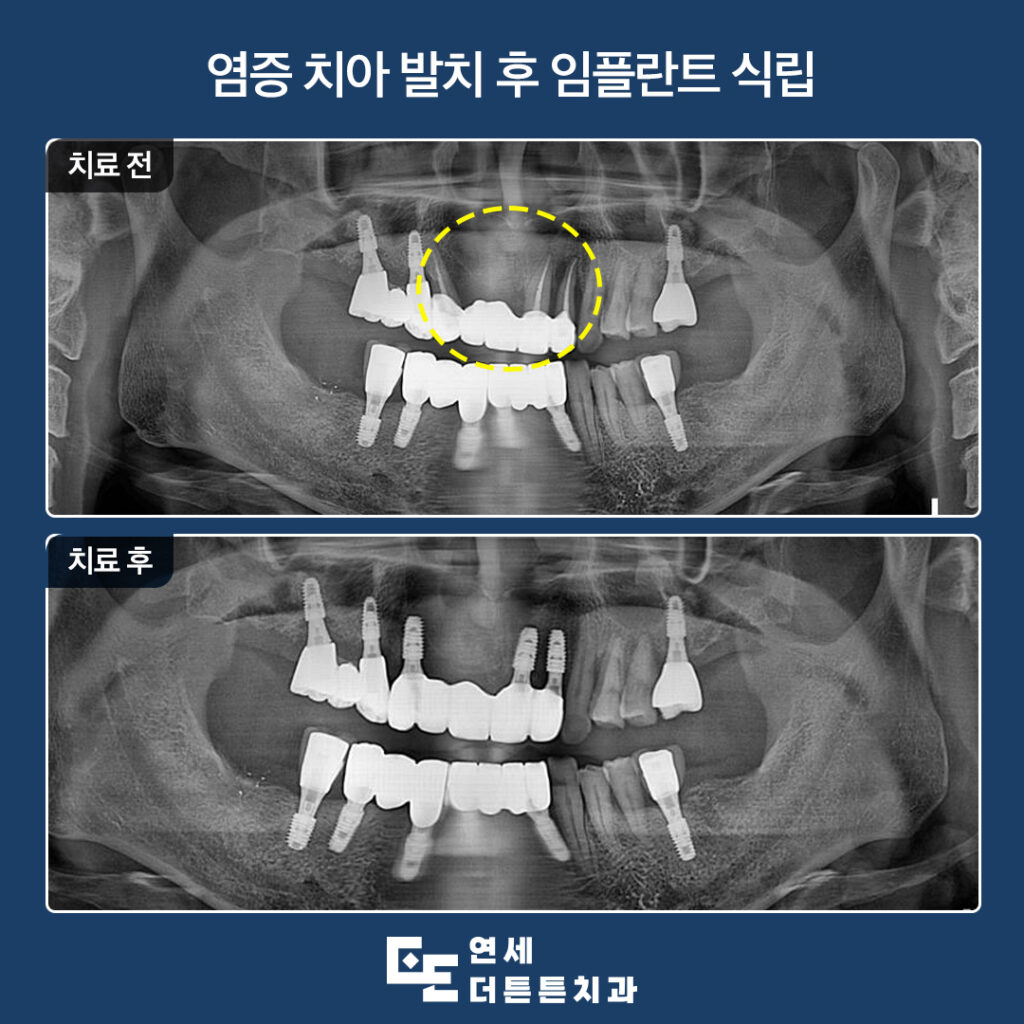

겉으로 보기에는 문제가 없는 듯 보였으나

파노라마를 촬영해 보니, 지탱하고 있던 양쪽

지대치 뿌리 쪽 염증으로 인해 잇몸뼈가 거의

남아 있지 않을 만큼 녹아 있었고

살려 쓰기에는 무리가 있다고 판단되어

발치 후 임플란트 식립 계획을 수립하였습니다.

먼저 기존의 브릿지를 제거하고

자연치들을 발치하였습니다.

수락산역치과 연세더튼튼치과에서

최종 보철물까지 완성한 모습입니다.